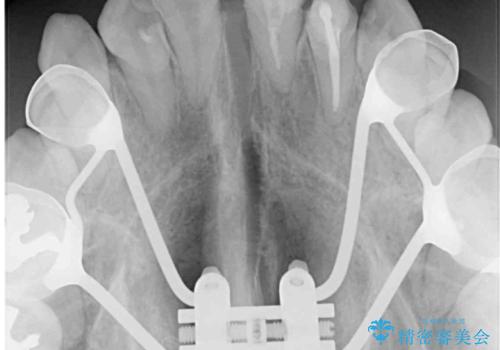

- 上下のデコボコと奥歯の咬みにくさを気にして来院された患者様です。

上顎骨の幅が下顎骨よりも小さいので、拡大装置により骨幅を広げて上下関係を改善し、その後インビザラインにて歯並びを整えることとしました。

上下の骨幅を改善したことで、スムーズに歯列矯正を行うことができました。

奥歯の咬み合わせを改善する必要があったため、治療は長期化しましたが、きっちりと仕上げることができました。